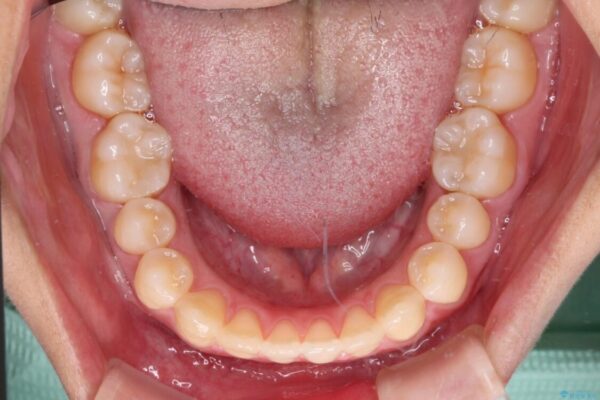

治療途中

• 隙間だらけの歯列 インビザラインで改善 治療途中画像